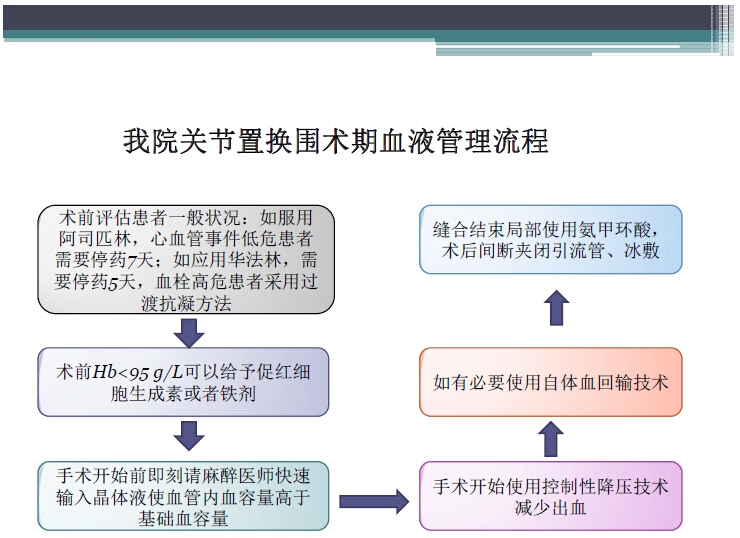

对于关节外科而言快速康复实际上是以病人加速舒适康复为目的,加强围术期的综合管理,包括疼痛和睡眠管理、血栓预防管理、感染预防管理、围术期血液管理,减少放置引流管、尿管、减少止血带应用,减少术后恶心呕吐,尽早进食,尽早康复等,逐步达到无血、无痛、无栓、无感、无肿、无管、无吐、无带等优良效果。为此,小编特邀王坤正教授等多位关节外科的专家参与撰写快速康复外科在关节外科的应用的主题文章,共话“人工关节置换快速康复”新理念,探讨建立符合我国特色的关节置换围手术期管理与快速康复体系,促进我国关节外科技术整体发展与提高。